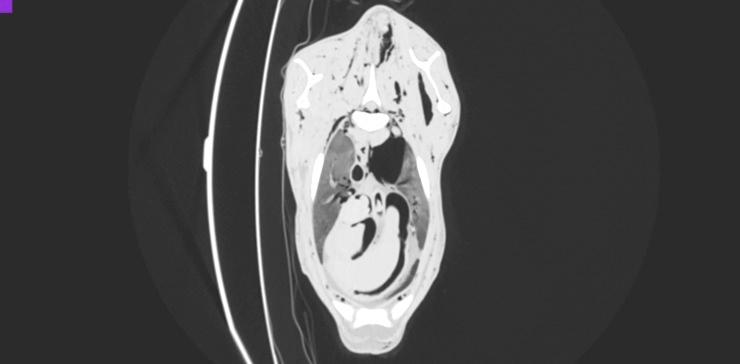

Evaluation of the usefulness of air as a negative contrast medium of blood vessels in goats in post mortem computed tomography (PMCT) and establishing the protocol with appropriate doses and timing of the contrast medium administration.

Thirty three goats were euthanized 10 to 300 min before the study. First, in 3 goats air was administered into the left or right common carotid artery at dose of 60, 100 and 120 ml/kg, and after each dose PMCT was performed in lateral recumbency. As the latter dose proved to visualize blood vessels best, following 30 goats were examined in the same manner but only with the use of air dose of 120 ml/kg. The quality of CT scans was evaluated independently by two board-certified radiologists.

RESULTS

In all studied animals the vascular system filled with air was clearly visualized on CT scans. In most of goats this amount of air revealed vessels smaller than 4 mm in diameter.

评估空气作为死后计算机断层扫描(PMCT)中血管负性对比介质的用途,并制定合适剂量和对比介质给药时间的方案。

33 只山羊在研究前 10 至 300 分钟被安乐死。首先,在 3 只山羊中,以 60、100 和 120 ml/kg 的剂量将空气注入左或右颈总动脉,每次给药后在侧卧位进行 PMCT。由于后一个剂量证明可以最好地显示血管,随后对 30 只山羊以相同的方式进行检查,但仅使用 120 ml/kg 的空气剂量。两名经过委员会认证的放射科医生独立评估 CT 扫描的质量。

结果

在所有研究动物中,血管系统都在 CT 扫描中清晰可见。在大多数山羊中,这种数量的空气揭示了直径小于 4 毫米的血管。